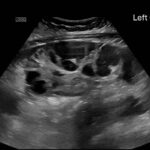

Ovarian hyperstimulation syndrome (OHSS) is a potentially life-threatening complication of assisted reproductive technology (ART). Here, we present the case report of a 30-year-old female undergoing infertility treatment who presented to the emergency department (ED) with nausea and vomiting, abdominal distention, and shortness of breath. On physical exam, she had notable ascites. Computed tomography (CT) of the abdomen and pelvis and pelvic ultrasound (US) revealed significant ascites and enlarged ovaries with multiple cysts. She was diagnosed with severe OHSS and admitted to obstetrics and gynecology (OBGYN) service for five days where she underwent intravenous (IV) hydration and paracentesis. This case report reviews the clinical presentation, categorization, management, and prevention of OHSS and provides examples of imaging findings consistent with the condition.